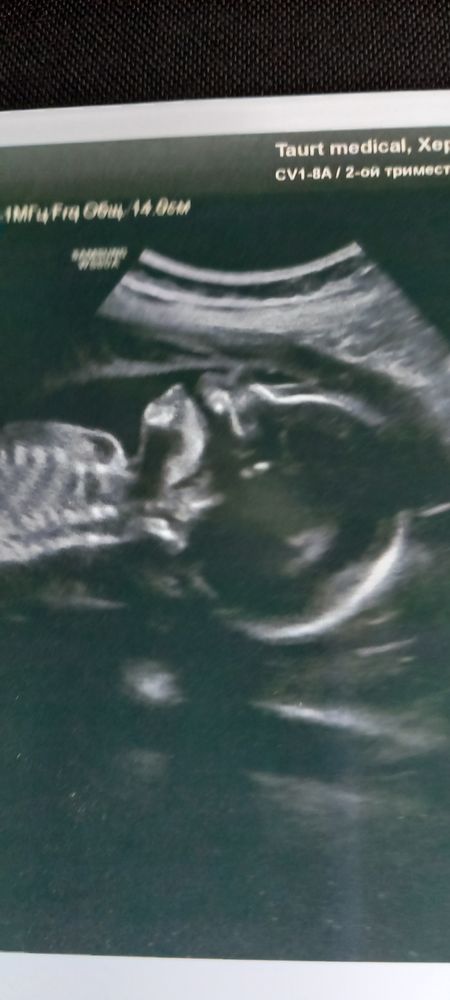

2й скрининг 20.3,вопросов больше чем ответов

Karmilla, так в том то и суть,что УЗИ в платной клинике. Там же и веду беременность. 3 врача делают УЗИ,гинеколог настояла чтоб вот к этому идти,мол чуть ли не спорога пороки видит если они есть. Но мне не понравилось. Пол специально просила не говорить. Мне выдали дымовую шашку. Через 2 недели на ДР мое будем узнавать кто же там.

Нормальный ИАЖ. И не понятно, почему пишет долихоцефалия. У нас в РФ норма ЦИ (это бпр разделить на лзр) от 71 до 84. У вас 74.

Светлана, спасибо. Успокоили. Просто на фотке вообще голова как голова ничего вытянутого я там не увидела. А долихоцефалия вроде это и значит. Может на разных сроках ЦИ по нормам разный? Или вы мне норму для второго скринига сказали?